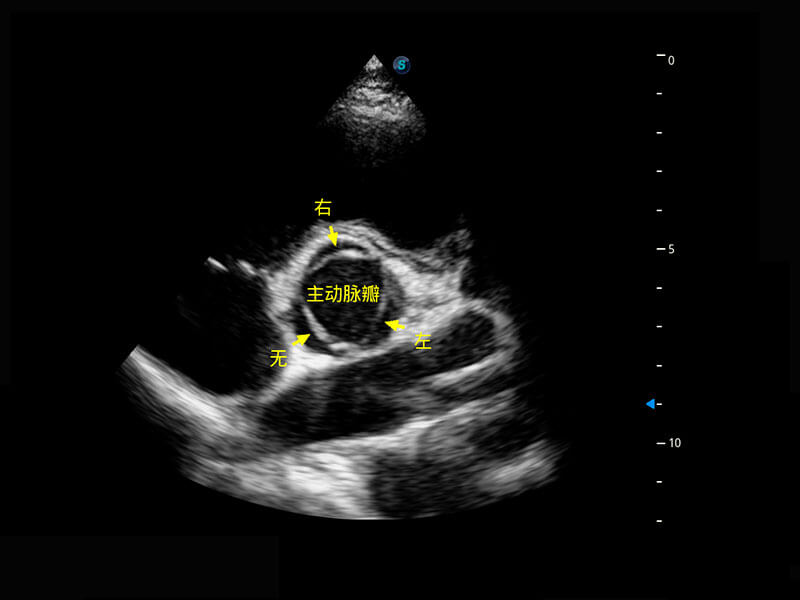

P60搭载一系列胎儿心脏成像技术,实现精细的胎儿心脏评估。

四腔切面